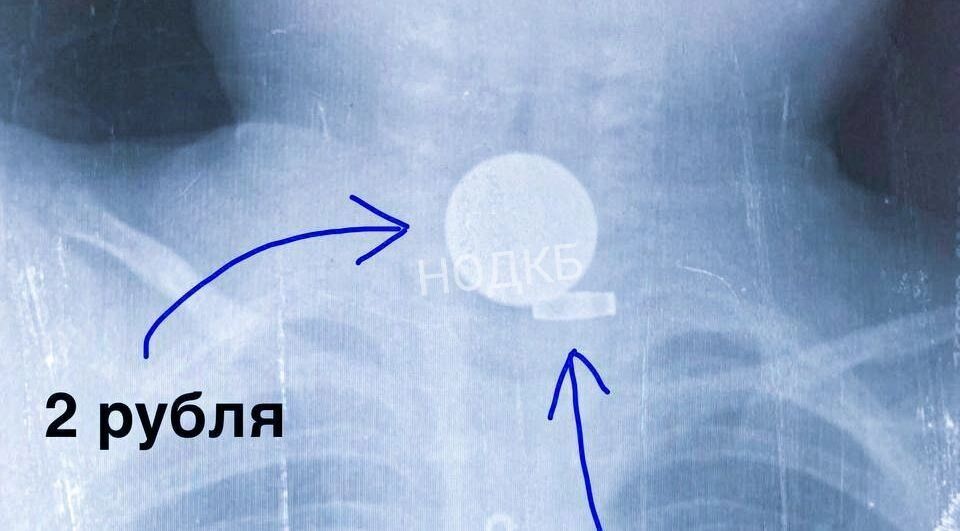

Монета

Мальчик месяц страдал от кашля, который не удавалось вылечить ни лекарствами, ни процедурами. В областной детской больнице врачи выяснили, что в пищеводе застряла двухрублевая монета. Как только ее достали, недуг мгновенно прекратился, и ребенок смог вернуться к нормальной жизни.